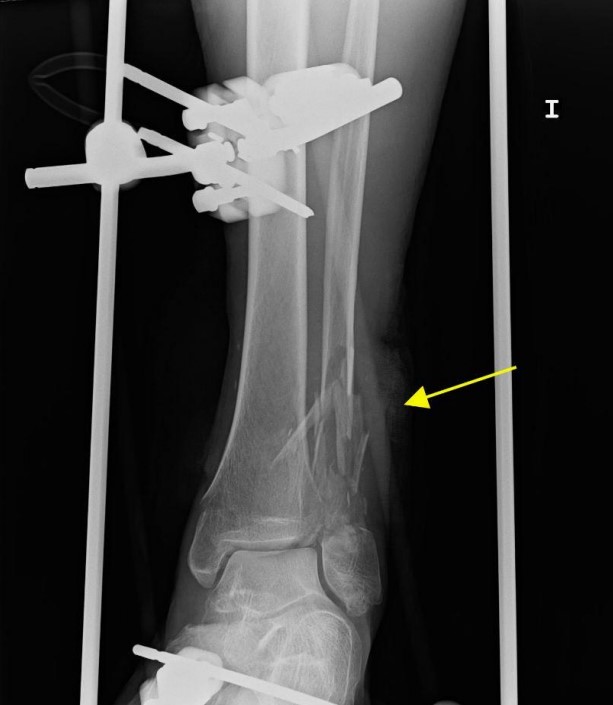

• 骨折后呼吸困難,警惕肺脂肪栓塞︱病例分享

骨折后呼吸困難,警惕肺脂肪栓塞︱病例分享

醫脈通編譯整理,未經授權請勿轉載。病例資料患者,男,61歲,跌倒后骨折,于急診室就診,并在數小時內出現進行性加重的呼吸急促。入院時,患者無發熱,血壓正常,室內空氣下血氧飽和度為92%,意識清楚,無局灶性神經功能缺損的癥狀或體征。其左下肢和右上肢畸形。既往病史無特殊。患者左下肢X線片顯示腓骨和脛骨骨折。胸片顯示上肺葉雙側肺泡混濁,這些不明確的斑片狀氣腔模糊是非